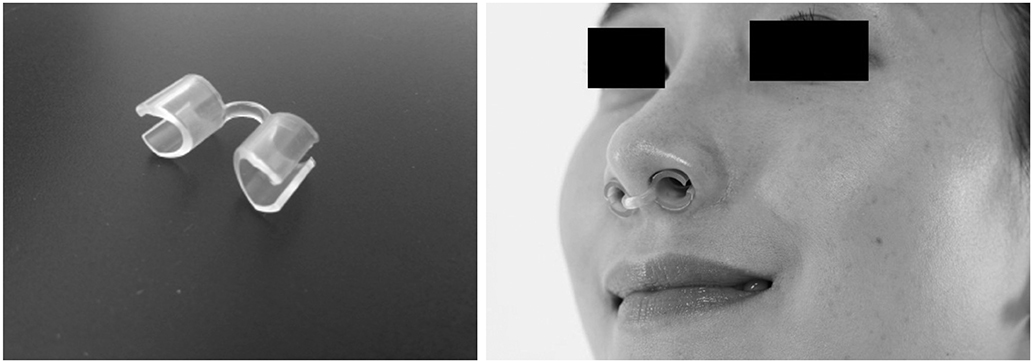

We aimed to evaluate effects of endonasal dilators (END) on sleep quality in patients with obstructive sleep apnea (OSA) by improving nasal airflow.

In 13 patients with OSA, changes of total nasal volume (TNV) and minimal cross-sectional area (MCA) before and after END use were evaluated. The change in peak nasal inspiratory flow (PNIF) was also measured. Subjects completed Epworth Sleepiness Scale questionnaire before and 2 weeks after END use. Finally, changes in apnea-hypopnea index (AHI), respiratory distress index (RDI), oxygen desaturation index (ODI), sleep time, sleep position and loudness of snoring (in decibels) were obtained by repetitive portable polysomnography.

END may be an effective adjunctive tool for patients with OSA with the potential to improve nasal airflow and daytime sleepiness.